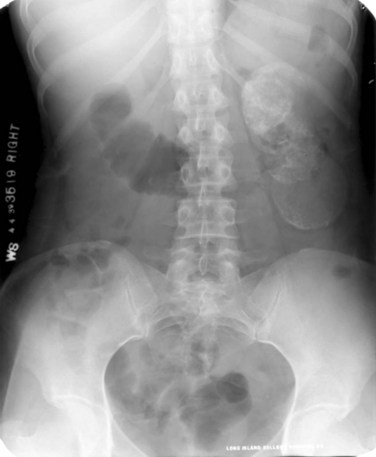

The most common findings on contrast-enhanced CT include renal parenchymal masses and scarring, thick urinary tract walls (ureter and bladder) and extraurinary tubercular manifestations particularly in miliary TB (Wang et al, 2003). Coalescence of caseating granulomata may lead to a renal mass (tuberculoma), which must be differentiated from renal cell carcinoma. CT allows for evaluation of renal function, grading of hydronephrosis and parenchymal scarring (Fig. 16–6). CT is most sensitive in detecting renal calcifications (Premkumar, et al, 1987). Most CT findings are in themselves nonspecific, and the collective interpretation of multiple findings in conjunction with the clinical picture is the best option in decision making (Wang et al, 2003).

Figure 16–6 CT after oral contrast medium in a patient with bilateral tuberculosis. The right kidney is hydronephrotic secondary to infundibular stenosis but has retained good function. The left kidney is an end-stage nonfunctioning atrophic kidney with calcification.